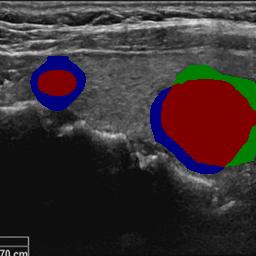

3.4.2 Contrastive Loss for Region-level Shape Learning

As outlined in Sec. 3.2, we propose to learn the segmentation shape by refining the feature representation of the foreground and background regions to achieve Eq. (2). Due to the features extracted by the network being inherently uncertain, multi-scale contrastive loss is exploited to optimize the inter-class variance and intra-class similarity of features sampled from the foreground and background label regions, ultimately refining the predicted foreground and background feature cluster extracted from the whole image domain.

Given high-confidence foreground areas and background areas . As shown in Fig. 3, the generic contrastive loss with a sampling scale size , denoted as

where and represent the sets of positive and negative feature embedding queues extracted from foreground and background feature map regions, respectively. denotes a foreground feature sample of size , while represents corresponding background feature samples. The anchor feature queue is selected from high-confidence foreground regions . The temperature parameter controls the slope of the loss function and its smoothness. Empirically, we evaluate the contrastive loss at scale sizes and , with .

The contrastive loss is designed to minimize the global distance between intra-class features (i.e., either both foregrounds or both backgrounds) in the embedding space and maximize the distance between inter-class features (i.e., foreground and background). Through this learning mechanism, the obtained feature representations effectively sharpen the classification boundaries between foreground and background regions.